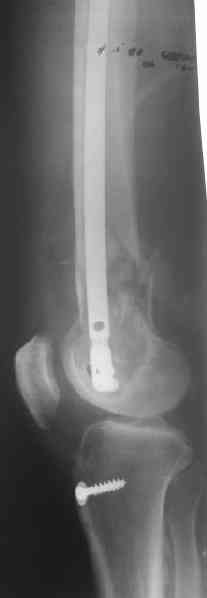

Длину восстановили, возможно, даже с изьбытком, ну да динамизируем пораньше. Введенные в овальное отверстие дистальые винты имеют угловую стабильность. Снимки приложены. Заранее спасибо за критику и комментарии.